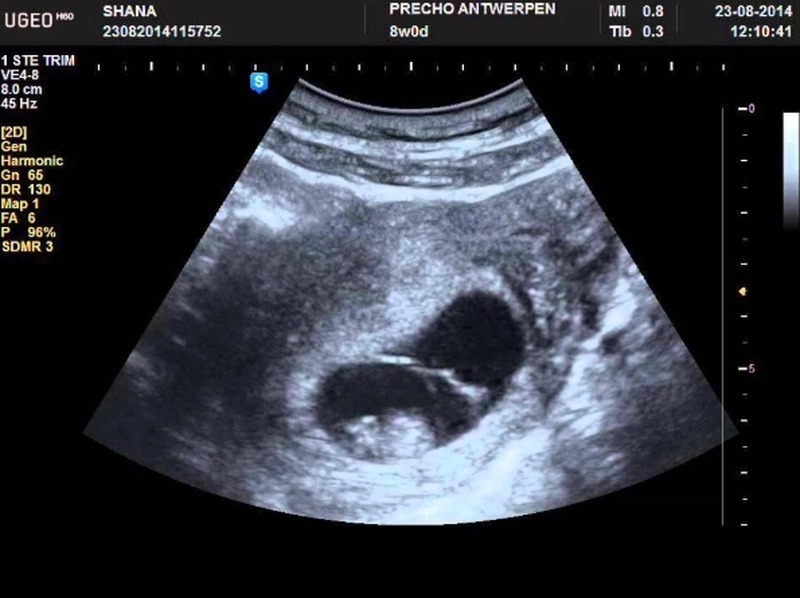

Hiện tượng xuất hiện yolksac trong siêu âm thai là dấu hiệu sớm cho thấy phôi thai đang phát triển bình thường trong tử cung. Yolksac thường được nhìn thấy ở tuần thai thứ 5 – 6 thông qua siêu âm đầu dò, xuất hiện dưới dạng một vòng tròn nhỏ, sáng bên trong túi thai. Sự có mặt của yolksac chứng tỏ quá trình thụ tinh và làm tổ đã thành công, là bước quan trọng trước khi quan sát thấy tim thai. Nếu sau tuần thứ 6 túi thai không xuất hiện yolksac, bác sĩ có thể nghi ngờ thai ngoài tử cung hoặc thai lưu.

Yolksac trong siêu âm thai hoàn toàn không nguy hiểm mà ngược lại còn là dấu hiệu tích cực cho thấy thai đang phát triển bình thường. Đây là cấu trúc tự nhiên và cần thiết trong giai đoạn đầu của thai kỳ, giúp nuôi dưỡng phôi khi nhau thai chưa hoàn thiện. Tuy nhiên, nếu yolksac có hình dạng méo mó, quá to hoặc quá nhỏ (thường >6 mm hoặc <2 mm) có thể là dấu hiệu cảnh báo bất thường trong quá trình phát triển của thai nhi. Khi bác sĩ phát hiện yolksac bất thường, thường sẽ chỉ định theo dõi sát và kiểm tra lại bằng siêu âm ở các tuần tiếp theo.

Thông thường, túi noãn hoàng có độ dày dưới 5 mm. Nếu yolksac dày hơn 5 mm hoặc có hình dạng bất thường, nguy cơ hình thành phôi thai không bình thường sẽ tăng cao. Điều này đồng nghĩa với việc tỷ lệ sảy thai trong tam cá nguyệt đầu tiên cũng cao hơn so với bình thường. Trong trường hợp yolksac quá dày hoặc bất thường, bác sĩ chuyên khoa sẽ theo dõi sát sao tình trạng sức khỏe của mẹ và thai nhi. Mẹ bầu có thể được chỉ định thực hiện thêm các biện pháp hỗ trợ y tế nhằm giảm nguy cơ sảy thai và duy trì thai kỳ ổn định.